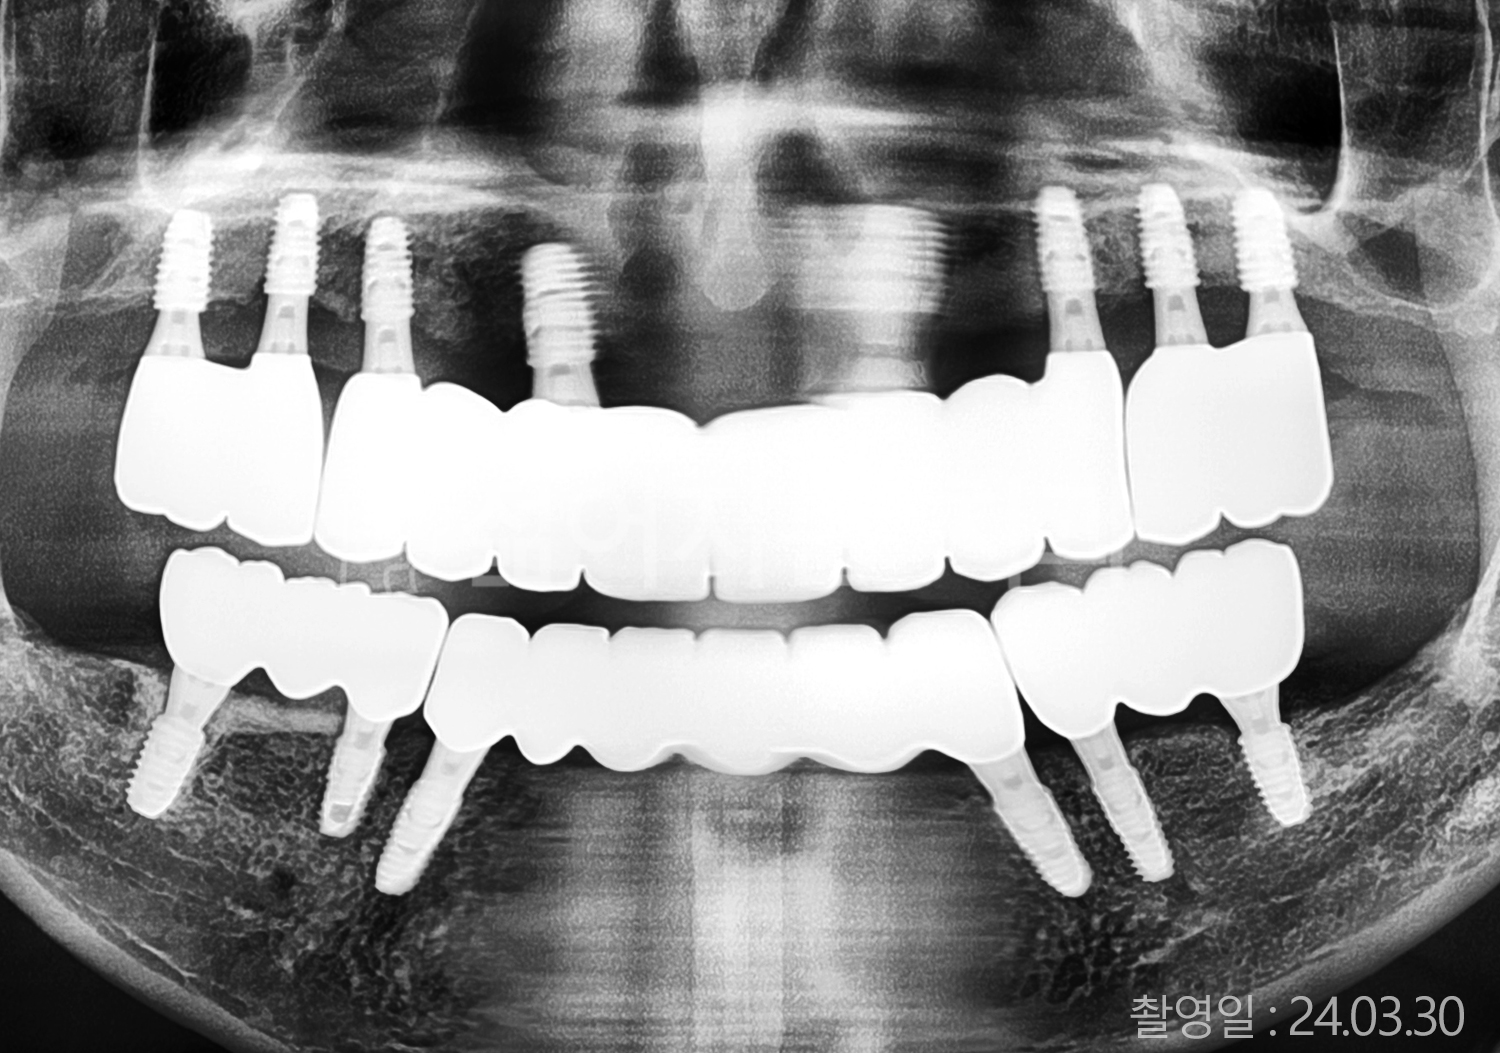

• 40대 전체치아 10개 이상 임플란트

• 50대 전체치아 10개 이상 임플란트

• 50대 고혈압, 당뇨, 고지혈증 전체치아 10개 이상 임플란트